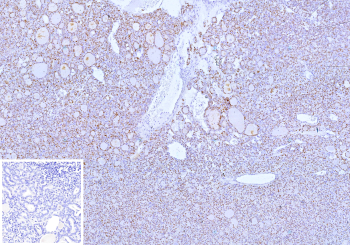

Thyroid Transcription Factor PAX8 Antibody immunohistochemistry in human thyroid tissue showing diffuse nuclear HRP-DAB brown staining in follicular epithelial cells. Paired box protein Pax-8 (PAX8) expression is localized to nuclei lining thyroid follicles, with uniform nuclear positivity surrounding colloid-filled lumina and clear preservation of follicular architecture. The staining is confined to epithelial cell nuclei with minimal signal in stromal components, while colloid material remains unstained. The nuclear pattern reflects transcriptional activity of this thyroid transcription factor and supports its role in regulating gene expression in follicular cells. Inset: negative control using PBS in place of primary antibody shows absence of specific staining. Heat-induced epitope retrieval was performed in 10mM Tris with 1mM EDTA, pH 9.0, for 45 min at 95oC followed by cooling at room temperature for 20 minutes.